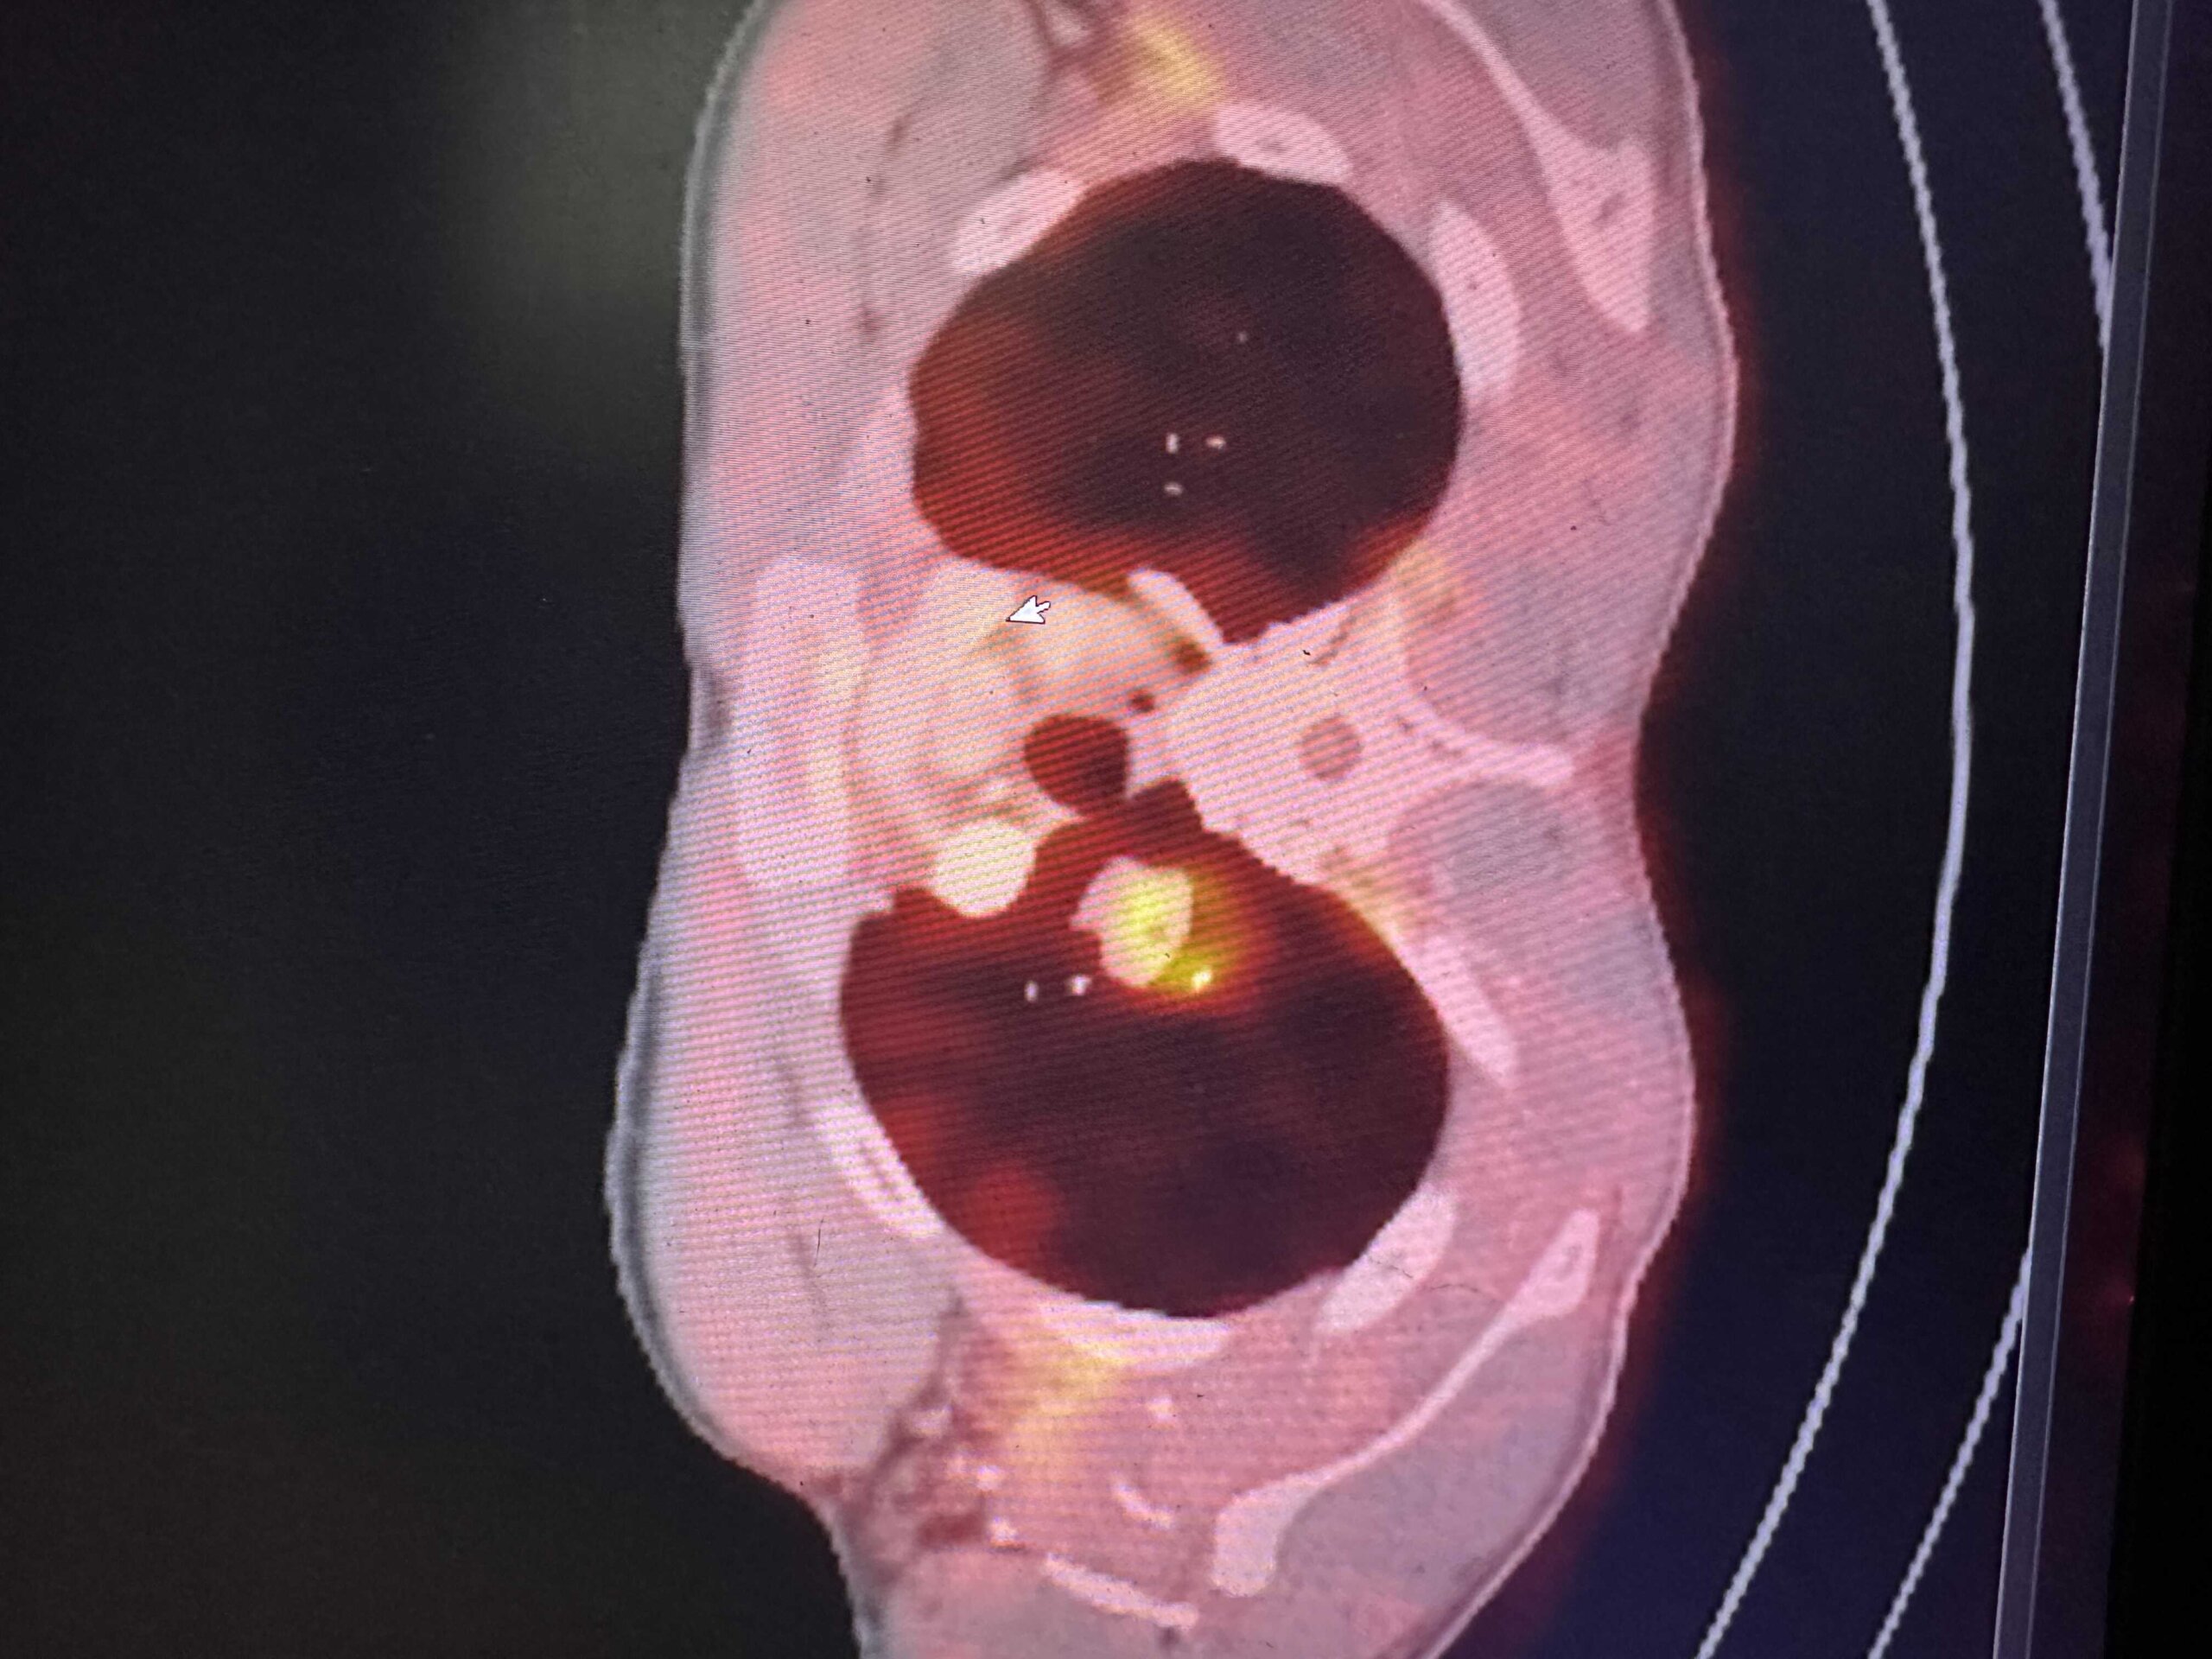

הביולוגיה של HNSCC

הבסיס הנדרש להבנת סרטן ראש-צוואר. מתחילים מהיסוד, עולה בהדרגה